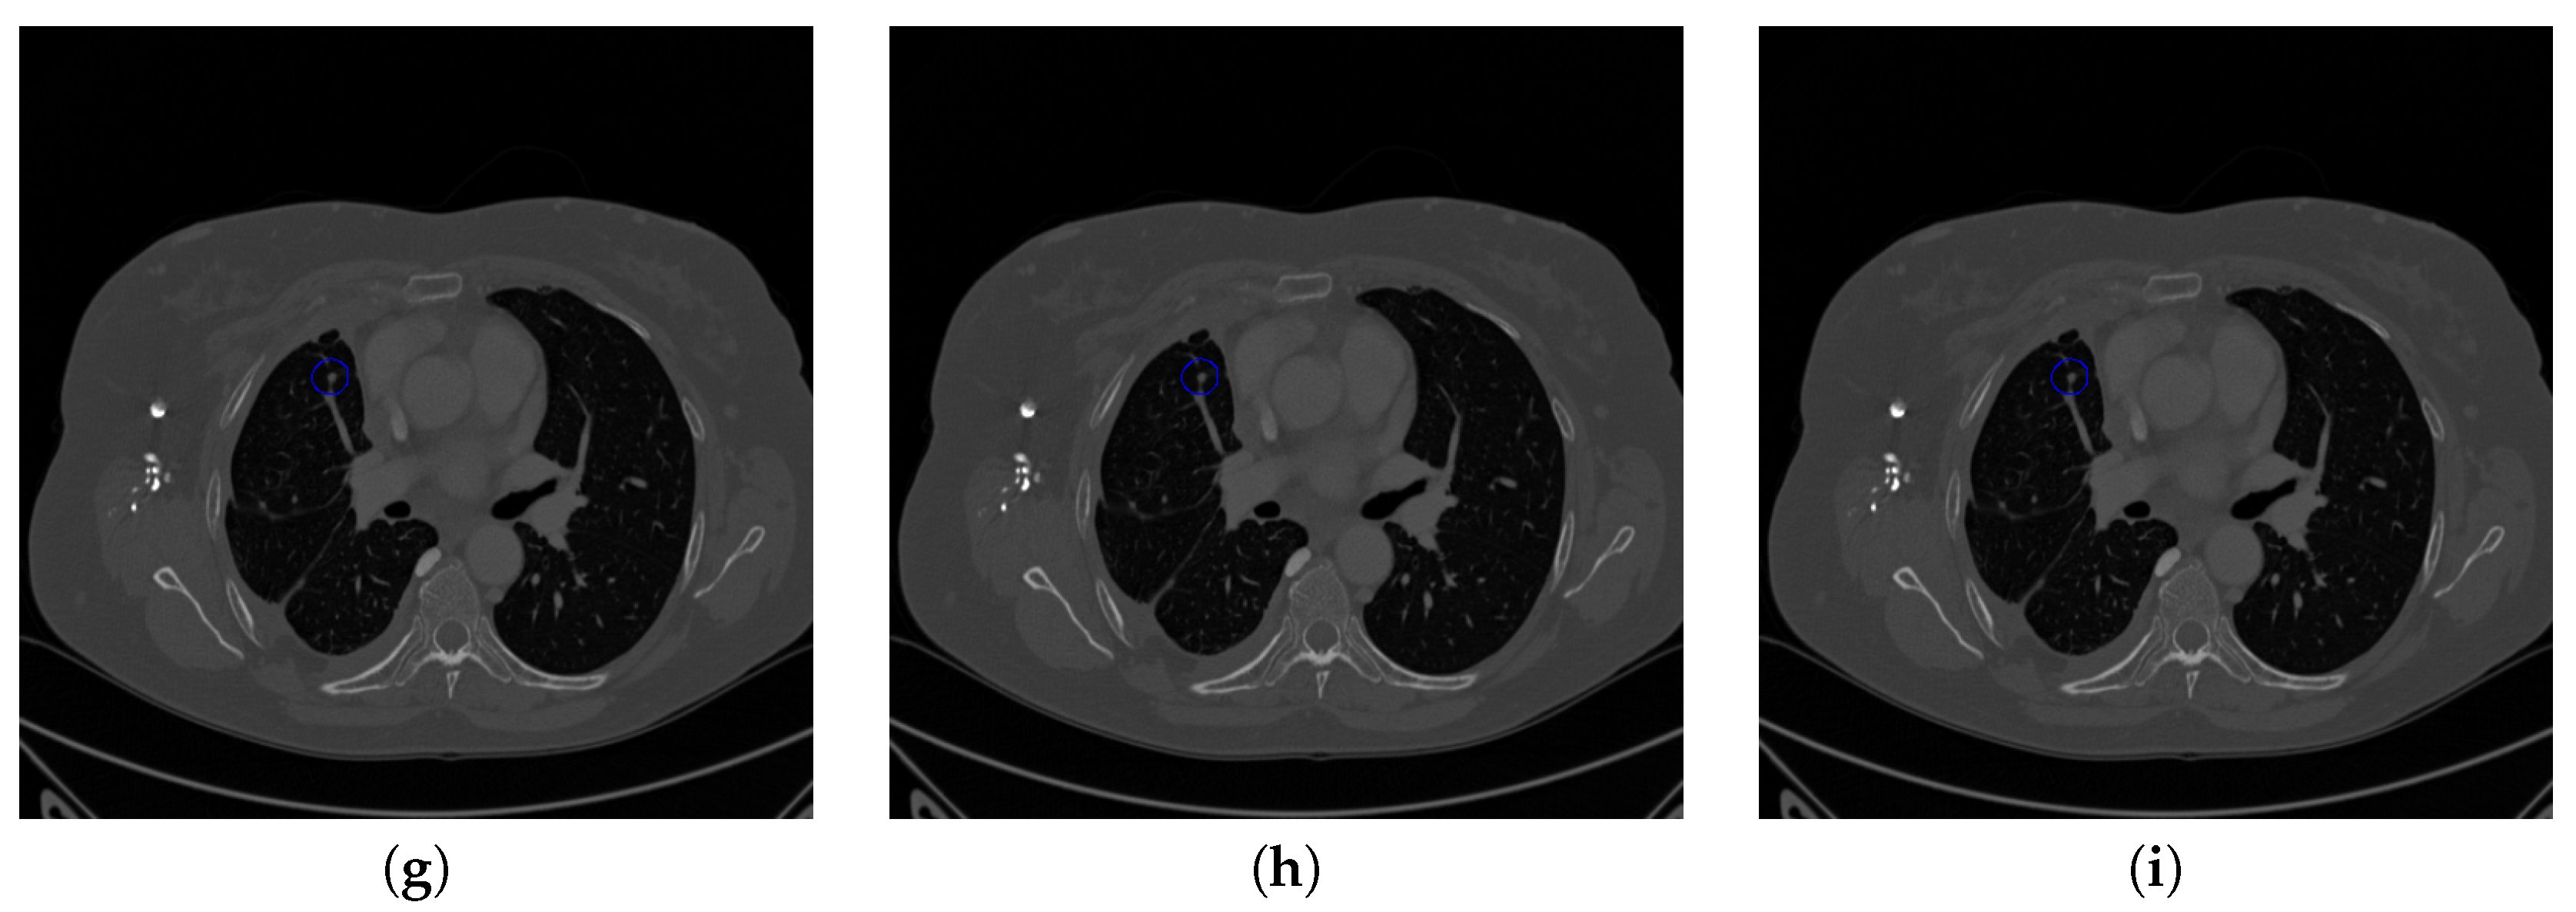

Figure 18. The result of detecting pulmonary nodules by different methods on another example image in LUNA16 dataset. Red circle represents the ground truth region of nodules, blue circles represent the correct estimation of pulmonary nodules, green circles represent the over-detected nodules, while yellow circles denote the nodules being omitted. (ai) are: ground truth nodule in the given chest CT image, nodule detected by 3D-FCN, MR-CNN, 3D-UNET, PRN-HSN, DCNN, CLAHE-SVM, MASK-RCNN and our proposed method.

Figure 17 and Figure 18 illustrates the performance of pulmonary nodule detection by different methods on two example images in the LUNA16 dataset. In addition, Figure 19 and Figure 20 illustrates the performance of pulmonary nodule detection by different methods on two examples images in the TianChi dataset. As marked by green circles in Figure 18b,c and Figure 19c, the 3D-FCN and MR-CNN directly detected the nodule candidates from the original CT image without pre-processing, resulting in the incorrect determination of non-nodule tissue outside lung as nodule since the outside-lung organs are not filtered out from the nodule candidates. The 3D-UNET and PRN-HSN add the lung parenchyma region segmentation stage before detecting the nodule candidates inside-lung, so they provide better performance than 3D-FCN and MR-CNN in decreasing the over-estimation rate. However, they still suffer from unsatisfactory results for the following reasons: (1) the lung parenchyma segmentation is generated by simple thresholding with morphological operations so the near-edge regions are lost, shown as the one marked by yellow circle in Figure 20d,e; (2) the convolution kernel used in nodule candidate detection of 3D-UNET is with a small receptive field to learn global features from the image, so it is likely to confuse some small tissues as true nodules with small sizes, shown as the one marked by green circle in Figure 18d and Figure 20d; and (3) the proposed hierarchical saliency network (HSN) in PRN-HSN for nodule candidate classification omits the information with different resolutions, resulting in that the small-size nodule within the weakened, low-resolution region cannot be correctly recognized, as shown by the yellow circle in Figure 18e. The DCNN method simply applies the Faster RCNN method to provide good performance with low computational cost, but it may omit the nodules on the parenchymal edge shown as yellow circles in Figure 20f. CLAHE-SVM method adds a contrast-enhancement pre-processing before the nodule detection, leads to better performance on detecting nodules in the low-contrast region. However, it is easily to over-enhance the small-size tissues and over-estimate them as nodules, as shown by the green circles in Figure 19g andFigure 20g. The detection is also implemented over the whole image, so the nodule on the parenchyma edge may be under-estimated show by the yellow circle in Figure 20g. The Mask-RCNN method provides better effects than the above methods because of the good performance of Mask-RCNN in object detection. However, the performance is not stable for the small-size tissues and the irregular-shape nodule, shown by the green circles in Figure 17h and Figure 19h, and the yellow circle in Figure 19h. The proposed method takes the advantage of a series of U-Net-like networks to perform the nodule detection following a “coarse-to-fine” order of inside-lung region detection, nodule candidate detection and nodule determination. The U-Net network is modified by embedding inception structure, replacing the convolution and pooling by dilated convolution, and adapting multi-scale pooling and multi-resolution convolution connection, for different requirements of the three stages, respectively. Moreover, it makes use of the MSE loss, VGG-19-based perceptual loss as the complement of dice loss to optimize the whole framework. Therefore, as shown in Figure 17i, Figure 18i, Figure 19i and Figure 20i, the proposed framework provides superior performance on pulmonary nodule detection with low over-estimation of non-nodule tissues at the same time.